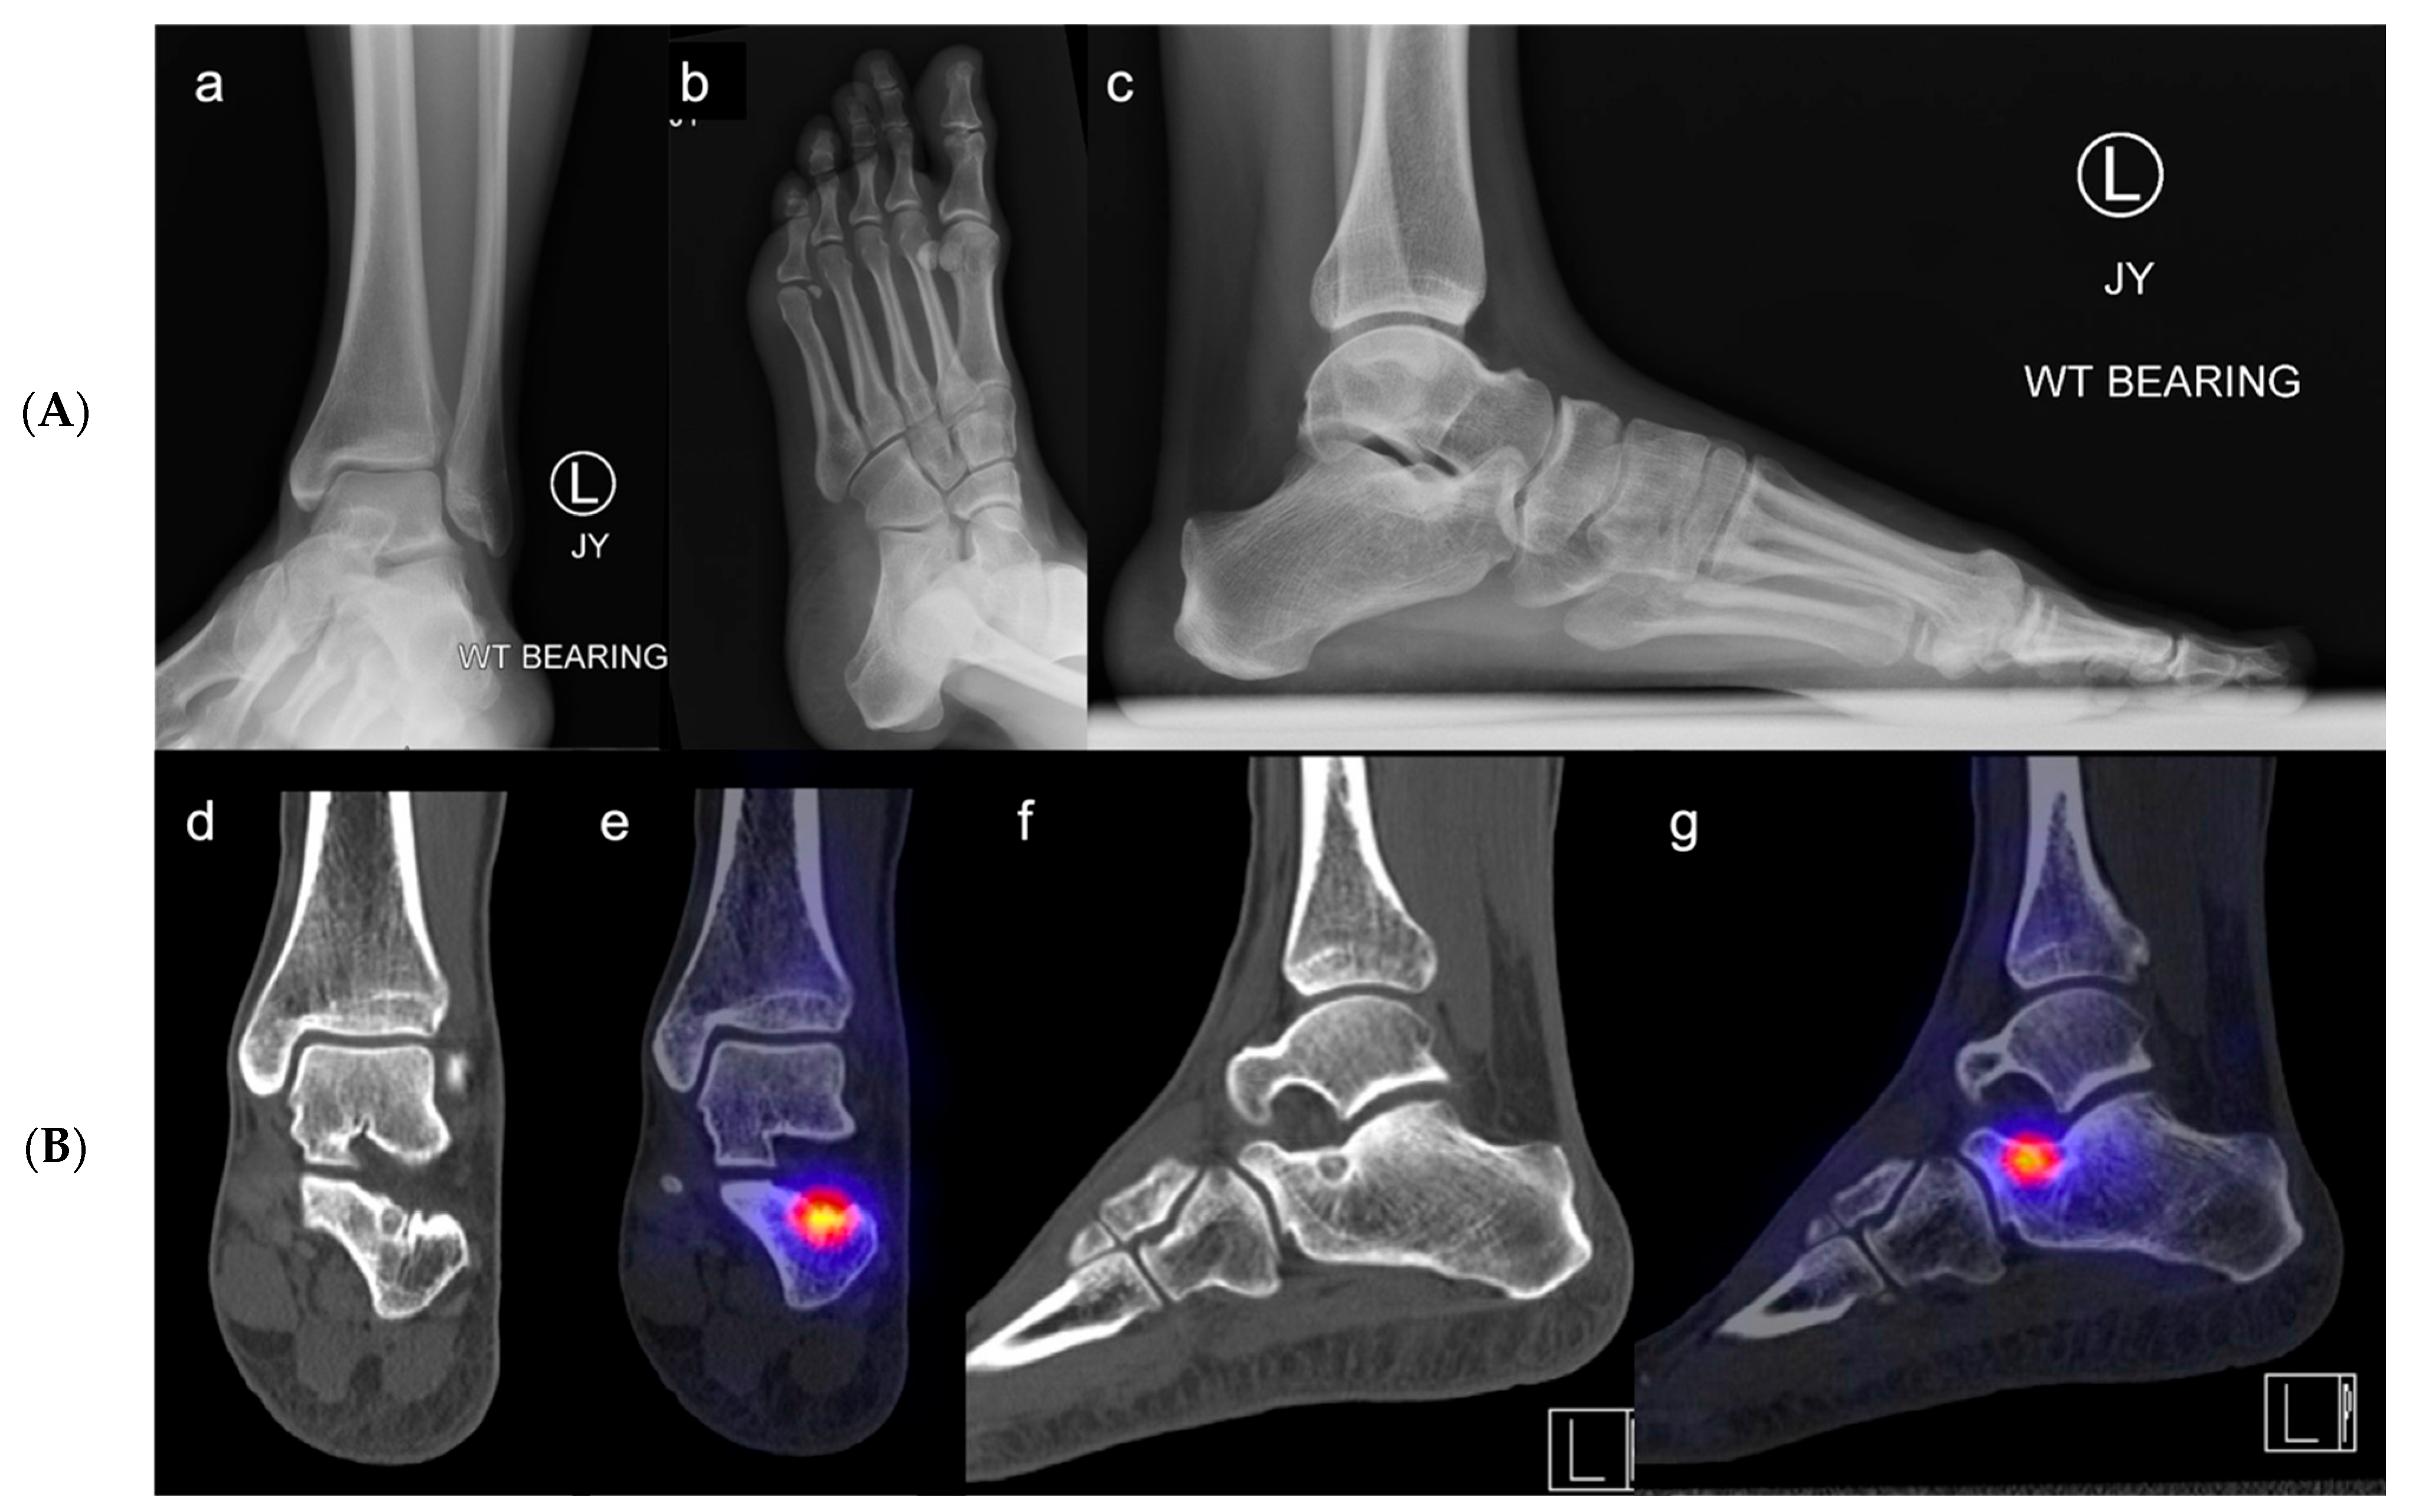

3.4.2. Radiographic Evaluation

3.4.3. Advanced Imaging

- Achong, D.M. Unsuspected Accessory Ossicle in Possible Sinus Tarsi Syndrome: The Value of Bone SPECT/CT. Clin. Nucl. Med. 2020, 45, e215–e216. [Google Scholar] [CrossRef]

- Martineau, P.; Pelletier-Galarneau, M. Sinus Tarsi Syndrome on Bone Scintigraphy with SPECT/CT: Spectrum of Findings. Clin. Nucl. Med. 2021, 46, e103–e105. [Google Scholar] [CrossRef]